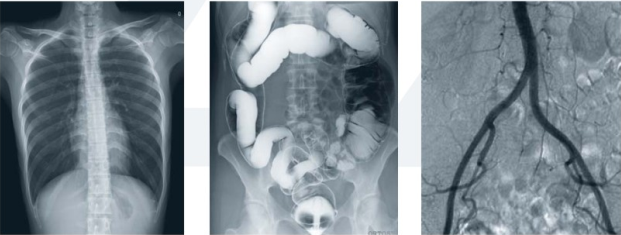

數字平板胃腸機屬于多功能X線機,除具有傳統胃腸機所有功能外,還有DR平板探測器X線攝影所有功能,主要用于消化道對比造影、消化道吞咽造影、全脊柱拼接攝影、全下肢拼接攝影、ERCP、泌尿系造影、“T”管造影、鋇劑灌腸、四肢造影、子宮輸卵管造影等各類檢查,是檢查消化道潰瘍、腫瘤、異物等疾病的主要方法之一。

數字平板胃腸機不僅可以做普通的胃、食管鋇餐透視,胸腹部的常規透視檢查,而且圖像更清晰,多了數字化處理過程,還可以實時點片,更便捷的獲得實時圖像,及時抓拍住病灶圖像,為患者留存影像資料。這就像我們的手機抓拍瞬間圖像保存到手機相冊一樣,能夠診斷早期食道癌、胃癌、小潰瘍等疾病。